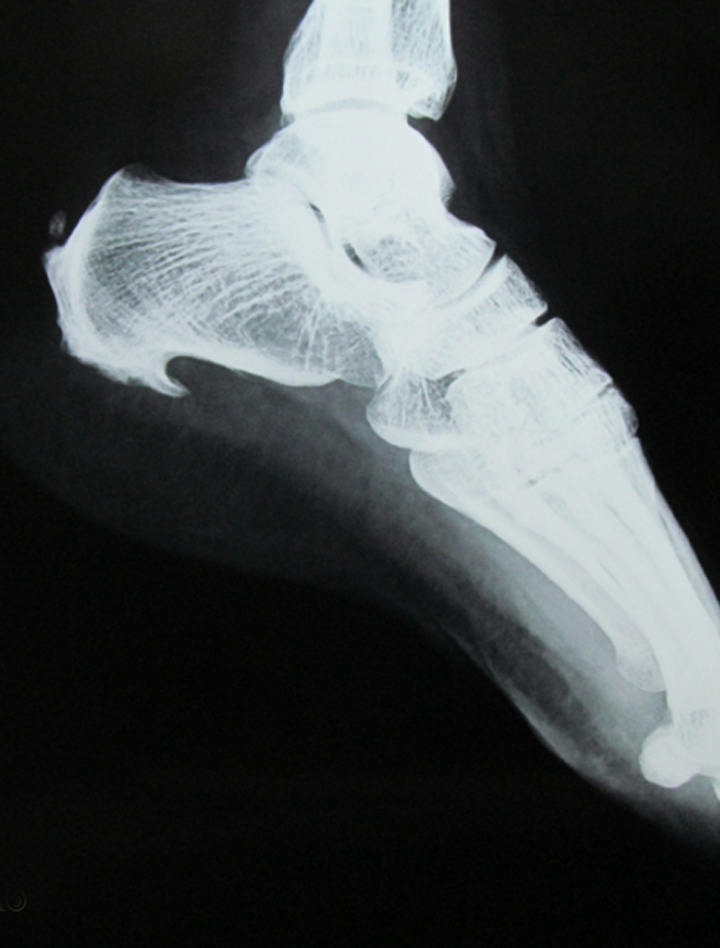

Heel spurs may be detected by using an X-Ray. It is a small osteophyte (or bone spur) located on your heel.

When a foot bone is exposed to constant stress, calcium deposits build up on the bottom of the heel bone. Generally, this has no effect on daily life. However, repeated damage can cause these deposits to pile up on each other,causing a spur-shaped deformity, called a calcaneal (or heel) spur. These tend to develop most in obese people, flatfooted people, and women who constantly wear high-heeled shoes.

Heel spurs are soft, bendable deposits of calcium that are the result of tension and inflammation in the plantar fascia attachment to the heel. Heel spurs do not cause pain. They are only evidence (not proof) that a patient may have plantar fasciitis.